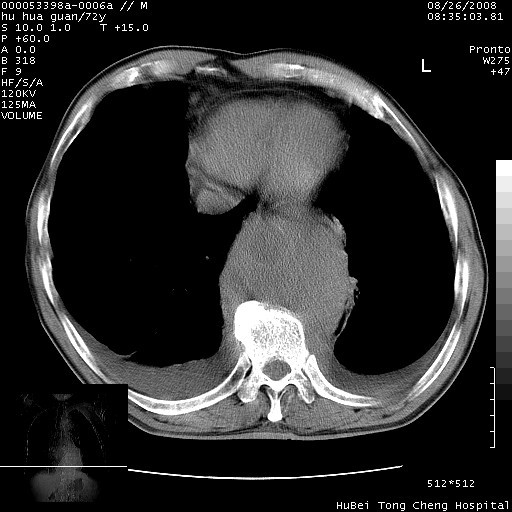

降主动脉前移位,后纵隔占位

后纵隔占位,降主动脉前移位;双侧胸腔积液;应排外食管病变侵犯血管可能;

1、右上肺结节病变,肺泡癌不除外,请随诊;左下肺近后纵隔病变,考虑纵隔型肺癌侵犯大血管可能;

2、右下肺背段少许炎症,双侧胸腔积液,右下肺纤维索条。